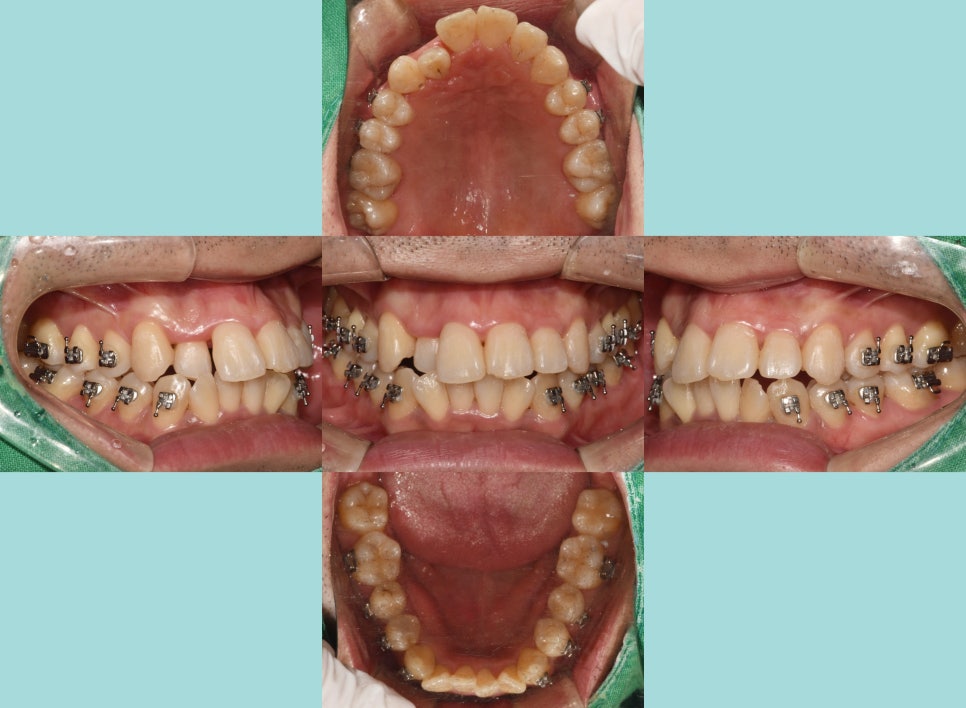

비발치로 진행 시,

비뚤어져 있는 이를 가지런히 맞춰줄 공간이 필요합니다.

치면에 브라켓을 붙여 어금니를 뒤로 이동시키며

공간을 형성합니다.

틀어져 있던 부분들이 서서히 이동을 시작하며

11번과 13번 사이에 간격을 줌으로써,

12번이 전방으로 나올 수 있는 길을 만들어

반대교합을 서서히 개선해 나갈 수 있습니다.

이에 따라 앞니 뻐드렁니 양상도

점점 후방으로 견인되어 들어가

돌출감을 줄여줄 수 있습니다.